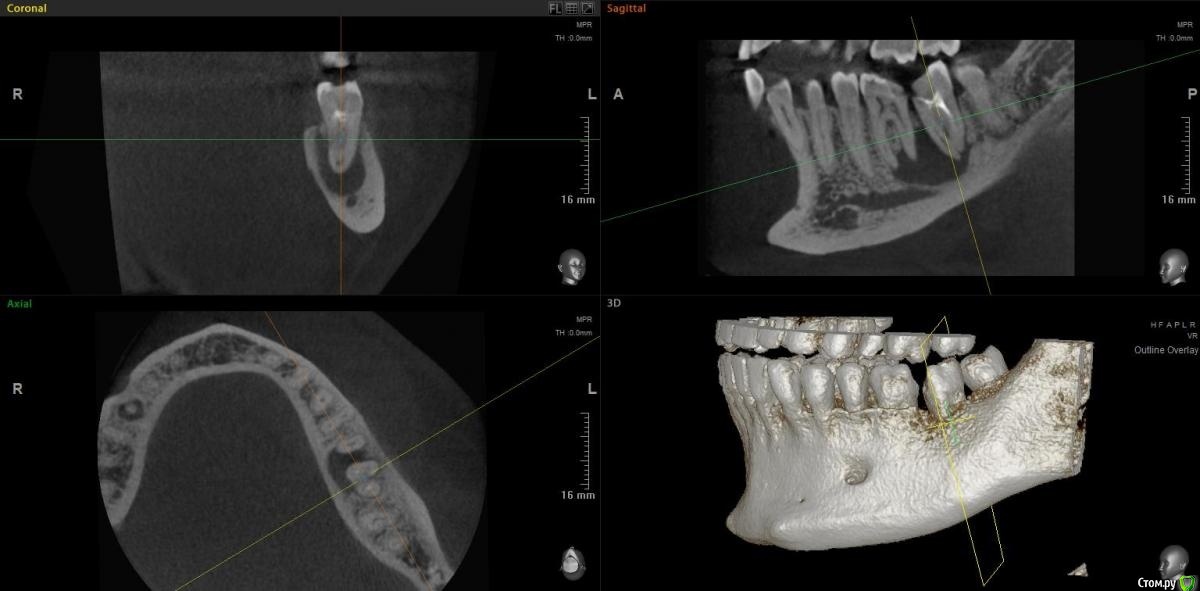

jm3300 Опубликовано 15 ноября, 2020 Поделиться Опубликовано 15 ноября, 2020 Коллеги, можно в данном случае вытянуть консервативно? Ссылка на комментарий

Irouil Опубликовано 15 ноября, 2020 Поделиться Опубликовано 15 ноября, 2020 Тут, похоже, не(только) корневая киста, язычно карман. Вопрос в терапию, наверное, но я скажу - нет 1 Ссылка на комментарий

red_butler Опубликовано 15 ноября, 2020 Поделиться Опубликовано 15 ноября, 2020 Имхо нужно в терапию, по данным срезам не увидел проблем с реэндо 2 Ссылка на комментарий

jm3300 Опубликовано 15 ноября, 2020 Автор Поделиться Опубликовано 15 ноября, 2020 Тут, похоже, не(только) корневая киста, язычно карман. Вопрос в терапию, наверное, но я скажу - нетвозможный карман тоже смущает Ссылка на комментарий

Дмитрий М Опубликовано 15 ноября, 2020 Поделиться Опубликовано 15 ноября, 2020 самого пациента ещё не видел. попросили КТ посмотретьок )) тогда понятноесли только из снимков то 36 пробовать сохранять, эндо и наблюдение а вот 37 больше за удаление был подобный случай, только киста немного меньше была но так же с вовлечением корней 36 и 37 терапевт хотела удалить оба, но решили оставить 36 полечить и наблюдать, а 37(разрушен не подлежал восстановлению) удалил, кисту почистил, ч/з 3 мес имплант. в итоге с 36 все хорошо 1 Ссылка на комментарий